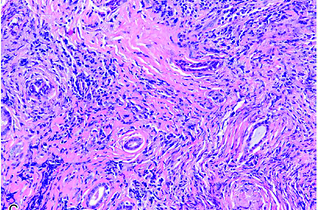

[最佳答案] IgG4相关疾病是一种自身免疫病。这种病主要是由于炎性纤维化,可以造成多个器官和系统的器官肿大组织破坏,甚至是器官功能衰竭。由于这种疾病血清当中的IgG4水平升高,所以以此命名。这类疾病通常会有1个或多个器官肿大。病理学会显示有淋巴细胞和浆细胞的浸润以及纤维化。治疗上以激素治疗为主,同时可以加用免疫抑制剂,比如硫唑嘌呤,吗替麦考酚酯,环磷酰胺等等。